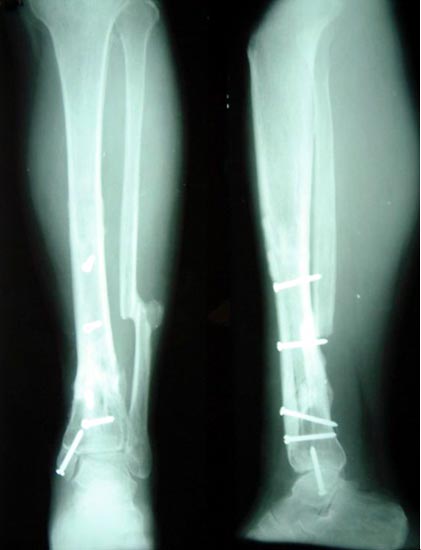

病例五、患者女性,30岁,胫骨多段开放粉碎骨折2年,骨不连,外固定架固定,皮肤大量贴骨瘢痕。

我们一期用腓肠肌内侧皮瓣修复皮肤贴骨瘢痕,4个月后行内固定和植骨。

带锁髓内钉固定骨折端提供支撑力,患者自体骨髓细胞经与松质骨和骨生长因子复合,使没有细胞的植骨材料变成了有细胞的活骨。骨折在9个月后愈合。